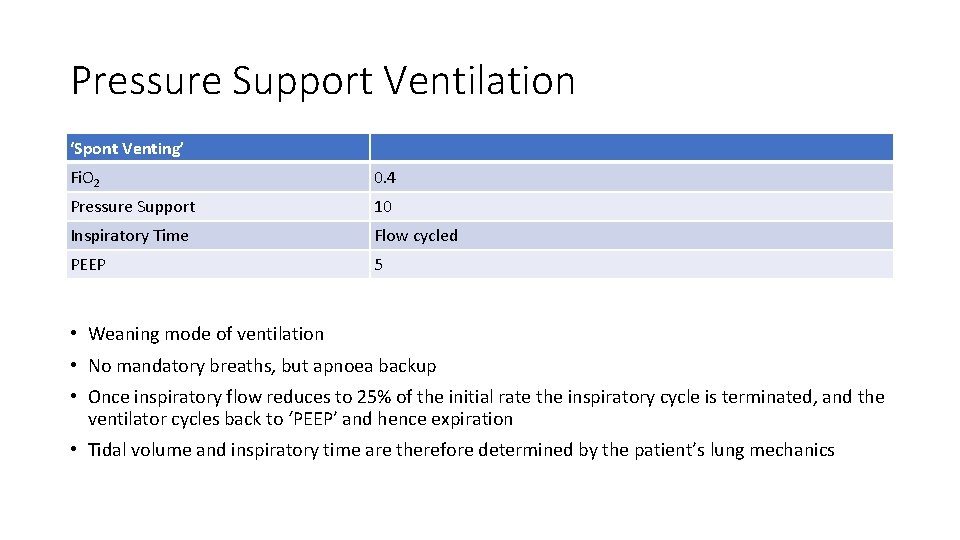

Pressure Support Ventilation ‘Spont Venting’ Fi. O 2 0. 4 Pressure Support 10 Inspiratory Time Flow cycled PEEP 5 • Weaning mode of ventilation • No mandatory breaths, but apnoea backup • Once inspiratory flow reduces to 25% of the initial rate the inspiratory cycle is terminated, and the ventilator cycles back to ‘PEEP’ and hence expiration • Tidal volume and inspiratory time are therefore determined by the patient’s lung mechanics